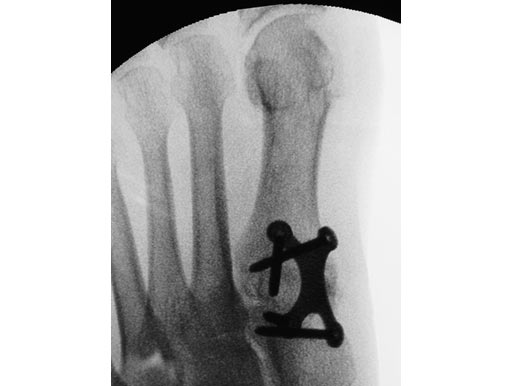

Case 2: 16-year-old male

Proximal first metatarsal growth-plate injury resulting in haluxvalgus. Arthrosis of first tarsometatarsal and second metatarsal hammer toe. Pain during activities and in general shoe wear.

Case provided by Carl Hasselman, Pennsylvania, USA

First MTP fusion and modified McBride with a distal softtissue release and second metatarsophalangeal (MTP) capsulotomy. A mini tight rope was used to hold and reduce the alignment of the first metatarsal. The X-plate was used to hold rigid fixation of the fusion. A K-wire was used for the second MTP capsulotomy.